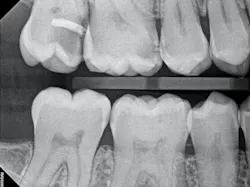

The iTero scanner was able to clearly define the delineation between the soft and hard tissue as can be seen in this image of the digital die trim (figure 3). Radiographs were captured on delivery revealing a clinically acceptable outcome for the patient (figure 4). Direct restorations were completed on teeth Nos. 3 and 4 during this visit.